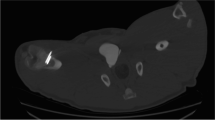

18 porcine femurs were obtained from a local abattoir. To prepare the lytic defects, for each specimen, square windows (12 mm sides) were cut into the dorsal cortex just proximal to the femoral condyles using a 2.5-mm drill and osteotomes (see Fig. 1). Via this window, bone and marrow were curetted out until the cavity could accommodate 15 ml of water (15 cm3, with water level flush with the outer cortex). 9 of the 18 bones were prepared to simulate a fracture at the cavity site. The fractures were produced by cutting into the bone using a fine saw blade to produce a discontinuity in the cortex. Fracture lines were of full cortical thickness. To be reproducible, all fracture lines extended from the mid-point of the window on the dorsal aspect of the bone circumferentially to the mid-point of the bone on the anterior cortex perpendicular to the longitudinal axis (Fig. 2).

The bone was stabilised to the work surface using two bench clamps. A system of eight thermocouples was then used to measure temperatures at the following sites: anterior aspect, cement surface, cement–bone interface, 5 mm from cement–bone interface, 10 mm from cement–bone interface. Thermocouples were then placed on the dorsal cortex (opposite side to the window) at the following sites: mid-point of cement bolus (worst case scenario position of radial nerve), proximal edge of cement bolus, 5 mm from proximal edge of cement bolus, and 10 mm from proximal edge of cement bolus (Fig. 3). Data from the thermocouples were processed by an 8-port Thermocouple Datalogger (PICO technology TC-08; St Neots, England). Data were recorded in an Excel spreadsheet (Microsoft Corporation, Redmond, Washington, USA).

A thermal imaging camera (FLIR systems, West Malling, England) was placed 1 m from the anterior cortex and centred over the position of the cement bolus. Images were taken every 20 s. The emissivity value was set to 0.99 [12] (Fig. 4).

Palacos (Heraeus, Wehreim, Germany) bone cement with gentamicin was vacuum mixed following the manufacturer’s instructions. Cement was injected into the cavity and finger pressurisation was used to ensure the cavity was filled and a 15 cm3 bolus was achieved. The surface of the bolus was left flush with the cortex as far as possible to leave minimal cement outside the bone. Cement did not extrude from the fracture lines (Fig. 5).